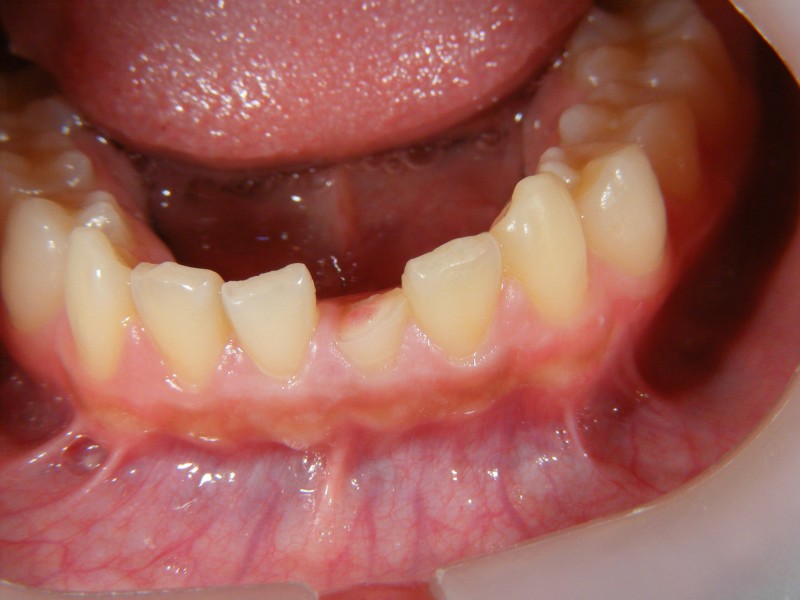

前歯が外傷で破折、神経が露出していたが、ダイレクトボンディングで修復したケース

前歯が外傷で破折、神経が露出していましたが、ダイレクトボンディングで修復したケースです。